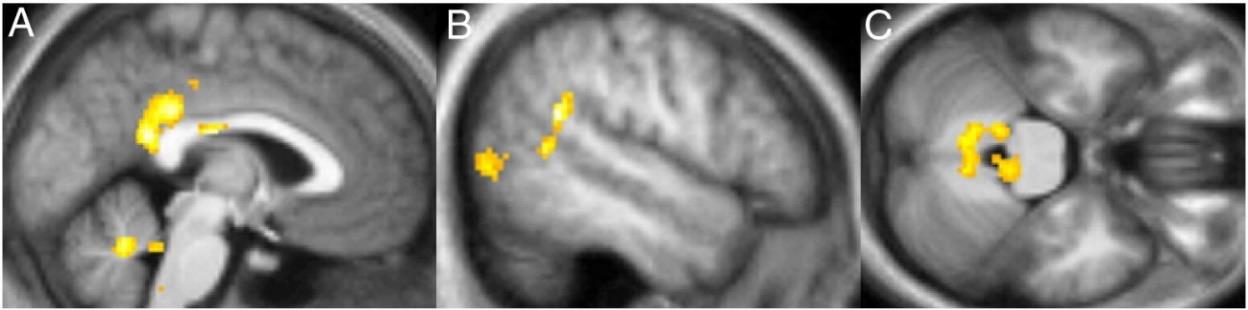

La figura 2, obtenida del estudio realizado por Tang et al. (2015), muestran las regiones del cerebro relacionadas con la práctica del mindfulness.

Figura 2. Regiones del cerebro asociadas con la práctica del mindfulness. Fuente: Tang et al., 2015, p. 217.

Los estudios basados en resonancia magnética funcional (”functional Magnetic Resonance Imaging”, fMRI) revelan un incremento de la activación en la corteza prefrontal dorsolateral, una región implicada en funciones ejecutivas. Estas funciones engloban procesos cognitivos de alto nivel que permiten planificar, tomar decisiones, regular emociones, mantener la atención, controlar impulsos y resolver problemas complejos que resultan fundamentales para afrontar situaciones nuevas o exigentes, ya que sustentan habilidades como la planificación y el autocontrol.

Asimismo, se ha observado una reducción de la actividad en la amígdala, lo que sugiere un mayor control sobre las respuestas emocionales automáticas, especialmente el miedo.